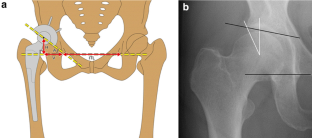

Fig. 1